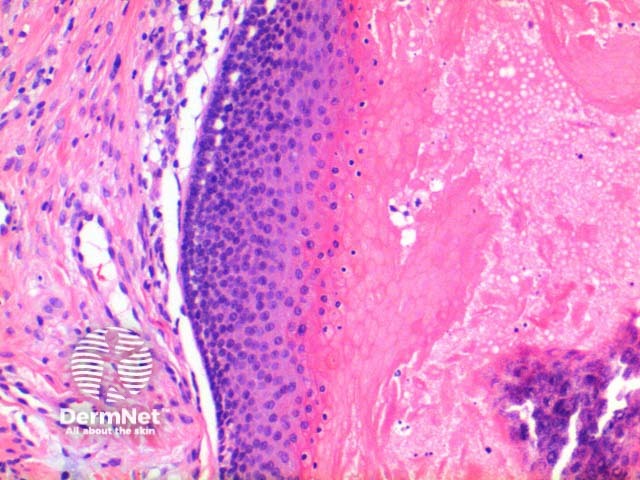

At low power the histological pattern seen in pilomatricoma is of a well-circumscribed nodulocystic tumour (Figure 2). While predominantly seen within the lower dermis, extension into the subcutaneous tissue is not uncommon. The tumour is comprised of a basaloid proliferation resembling the hair matrix cells, which matures into structureless eosinophilic cells lacking nuclei called shadow cells (Figures 3 and 4). The shadow cell area represents differentiation towards the hair cortex. Frequently there are areas of calcification within the shadow cell regions (Figure 5). A histiocytic infiltrate with multinucleated cells forms at sites of rupture (Figure 6).

Figure 3

Figure 4